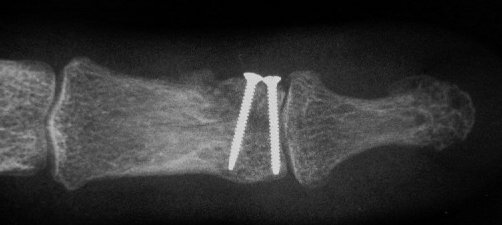

Clinical Example: Unicondylar proximal phalanx head fracture with micro screws

Unicondylar fractures of the phalangeal head are common, frequently unstable and unacceptably displaced. Although some may be treated successfully with percutaneous reduction and fixation, many require open reduction. In these cases, the screws were put right through the collateral ligament and sunk into the cortex. I think the simplest way to do this is to reduce and stabilize with two K wires, then remove the wires and replace with screws, one at a time, so reduction is maintained throughout. 1mm=39/1000" Kwire, so doing the math, here is how you choose the right sized Kwire to use as both drill and provisional fixation:

With two screws, bicortical fixation is not needed. The video below illustrates the steps involved, which are the same with either open or percutaneous fixation.